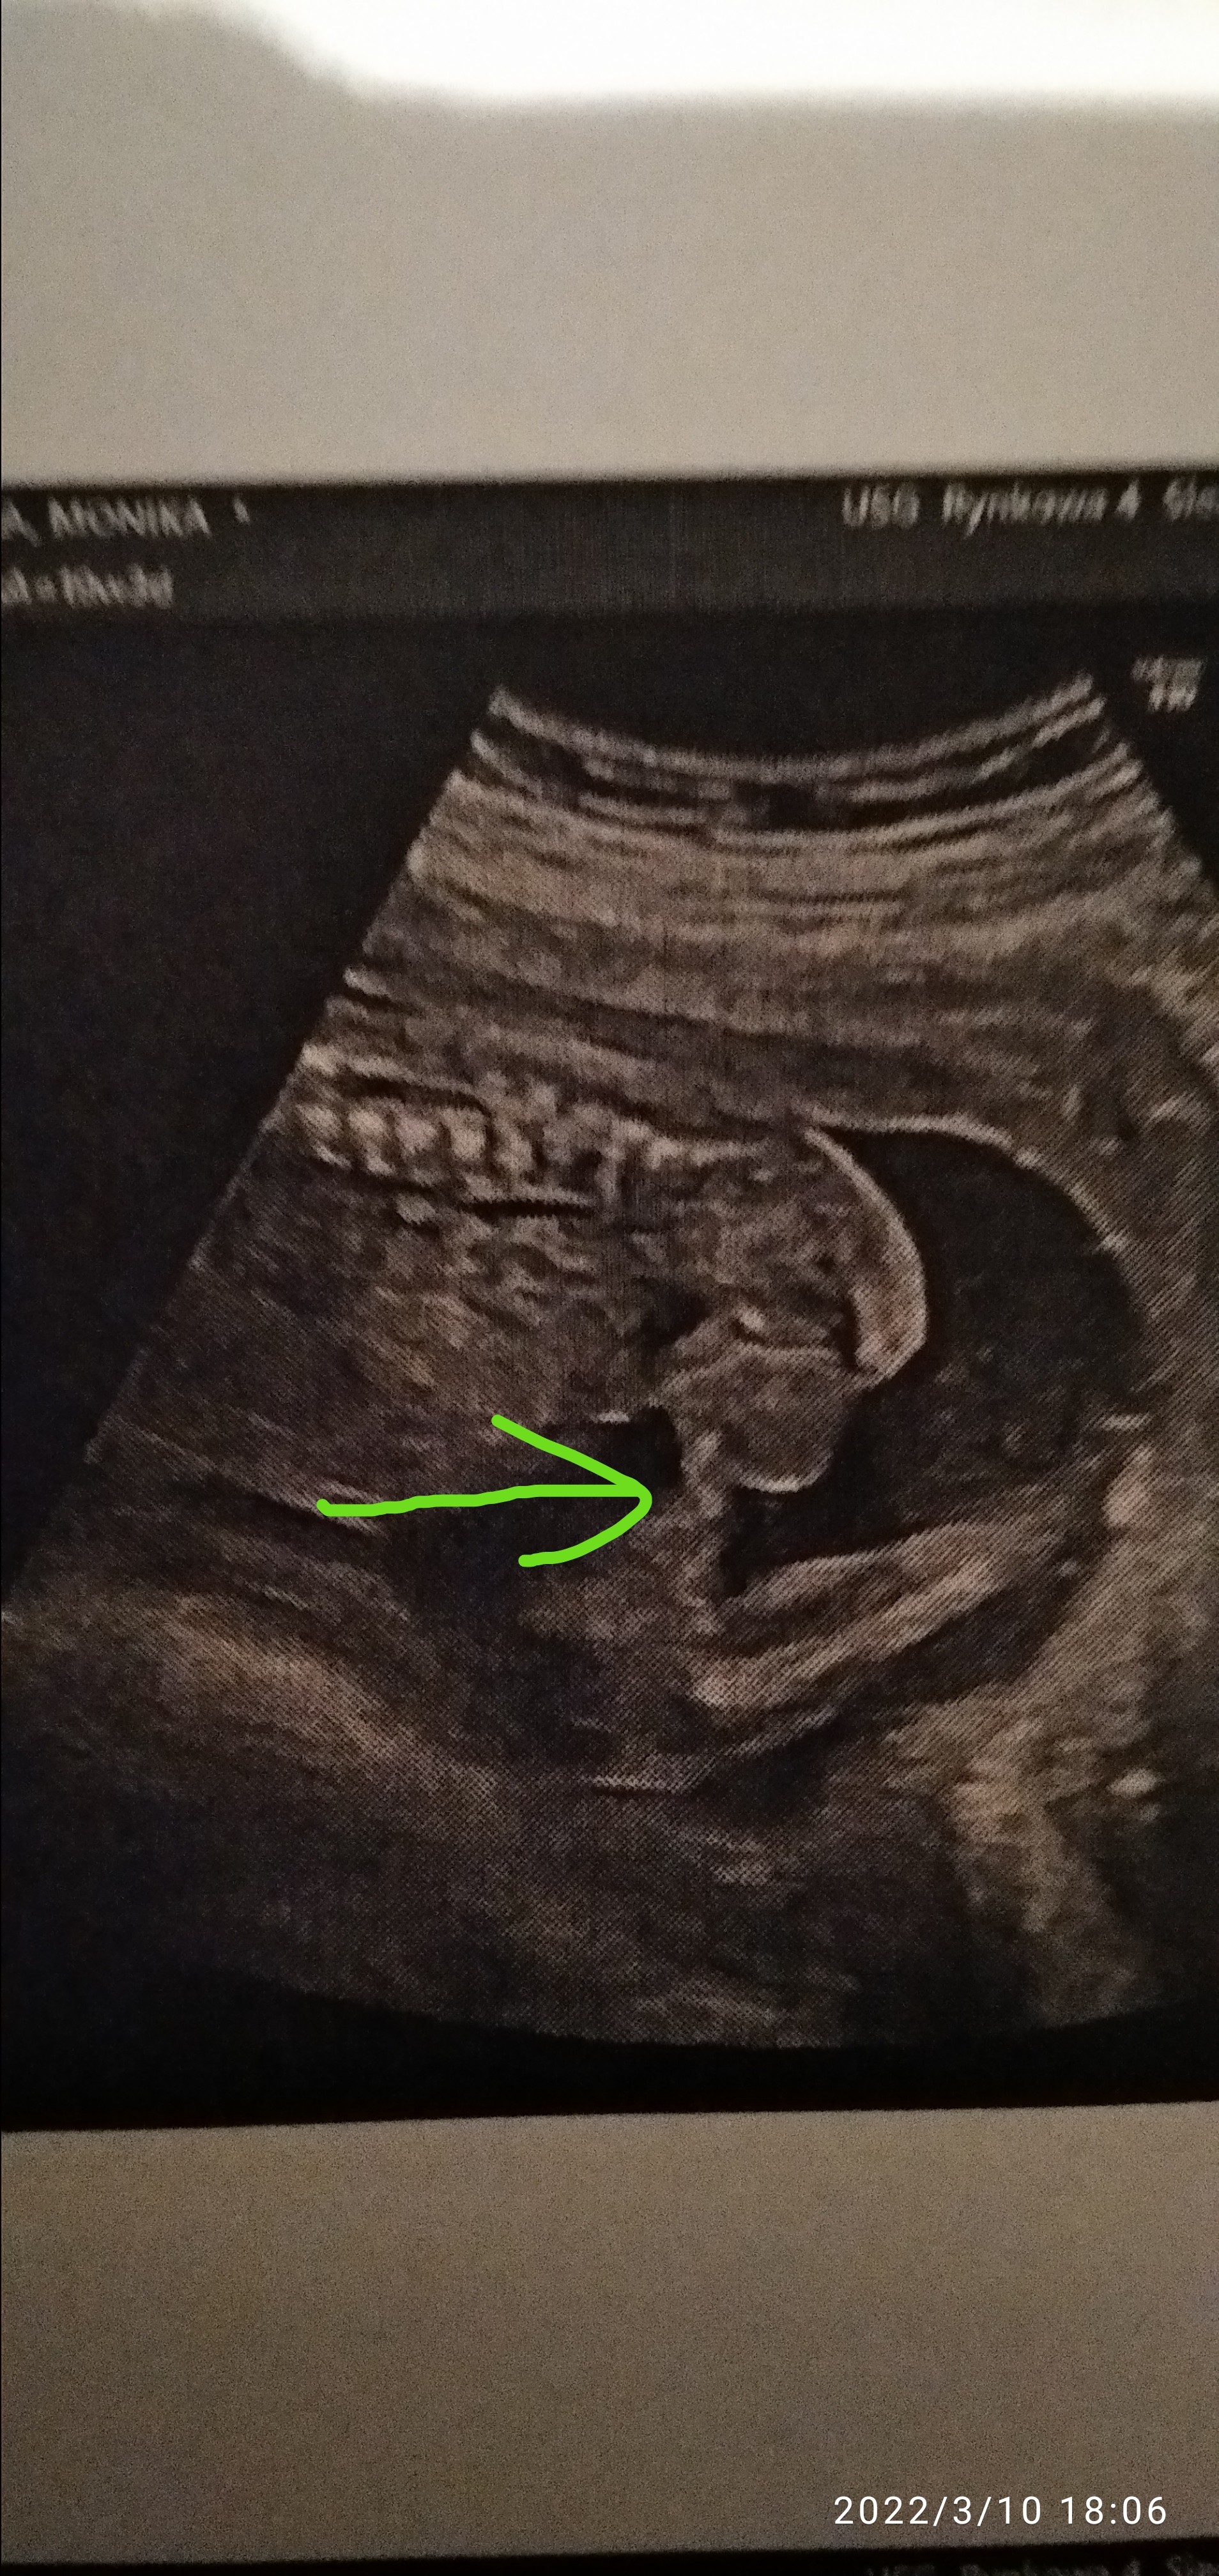

Cześć kobietki, skorzystam z tego wątku, bo na innym nikt nie odpisuje. Mam USG z 19 tygodnia ciąży, moim zdaniem jest to chłopiec, ale wprost lekarz nic nie powiedział. Jedynie skomentował, że widać w którym kierunku idzie płeć dziecka. Ja nie chcąc zrobić z siebie głupiej, nie dopytywałam. Zdjęcie jest z całkiem innej perspektywy, niż te wszystkie, które mamusie tutaj wstawiają.

Szkoda że to zdj z boku a nie od dołu. Na tym zdj może być to jądro tak mi się zdaje

Mamy, a myślicie, że to może być zwisający siusiak? Czy ja po prostu widzę to co chcę widzieć 😂

Ciężko powiedzieć w 100% ale wyglada jakby faktycznie były tam jąderka 😁